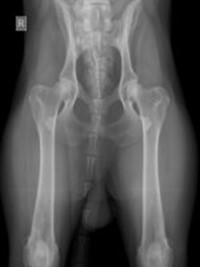

Le displasie possono essere diagnosticate precocemente con esami radiografici eseguiti dal quinto/sesto mese di vita. Questi esami, effettuati in sedazione, includono proiezioni specifiche per anca e gomito e sono essenziali per intervenire tempestivamente.

Tutti i cani che da adulti avranno un peso di 15/20 kg sia di razza che meticci sono soggetti alle displasie. Tale esame può essere eseguito dal quinto/sesto mese di vita quando i meccanismi degenerativi sono al loro esordio.

Spesso il cucciolo è asintomatico perché solitamente inizia a zoppicare solo dopo aver terminato la crescita. L’esame prevede una visita ortopedica con studio radiografico in sedazione.

Nello specifico lo studio dell’anca prevede ben 4 proiezioni (antero posteriore standard, in distrazione, a rana e dar).